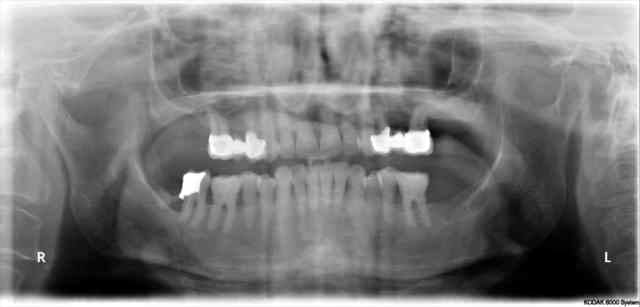

patiente envoyée pour ex° de 26 par un neurologue

souffre depuis 18mois, le bridge à 2ans

Déjà, les couronnes me paraissent bien débordantes

Deuxièmement, je ne vois pas de traitement canalaire sur ces dents. Peut etre souffrent elles de pulpite chronique

L'os entre 24 et 26 semble très bien en plus.

demain je chasse, mais lundi, je vais prendre le temps de modeliser le scan, pour controler les apex

je recois un scan , je regarde tout simplement si pbs au niveau des apex!Il n'y a rien de particulier

je regardais aussi si les dents etaient saines avant le bridge